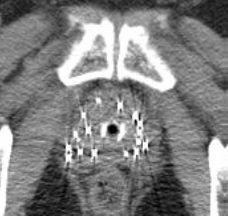

挿入後のX線写真を図1bに示します。 通常50~80個程度の小線源を挿入します。

前立腺やシード線源の状態を確認するため、13-14時ころにCT スキャンとレントゲンなどの検査を行い、排尿の管を抜きます。その後、放射線の線量を測定し、規定の放射線量を下回っていることを確認して、部屋を自由に出ることが出来ます。